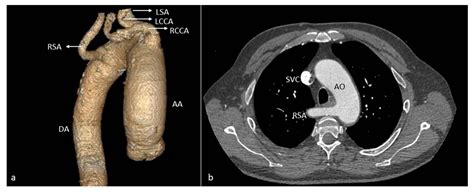

CT Angiography for Aortic Arch Anomalies: Prevalence, Diagnostic Efficacy, and Illustrative Findings

TitleCT Angiography for Aortic Arch Anomalies: Prevalence, Diagnostic Efficacy, and Illustrative Findings